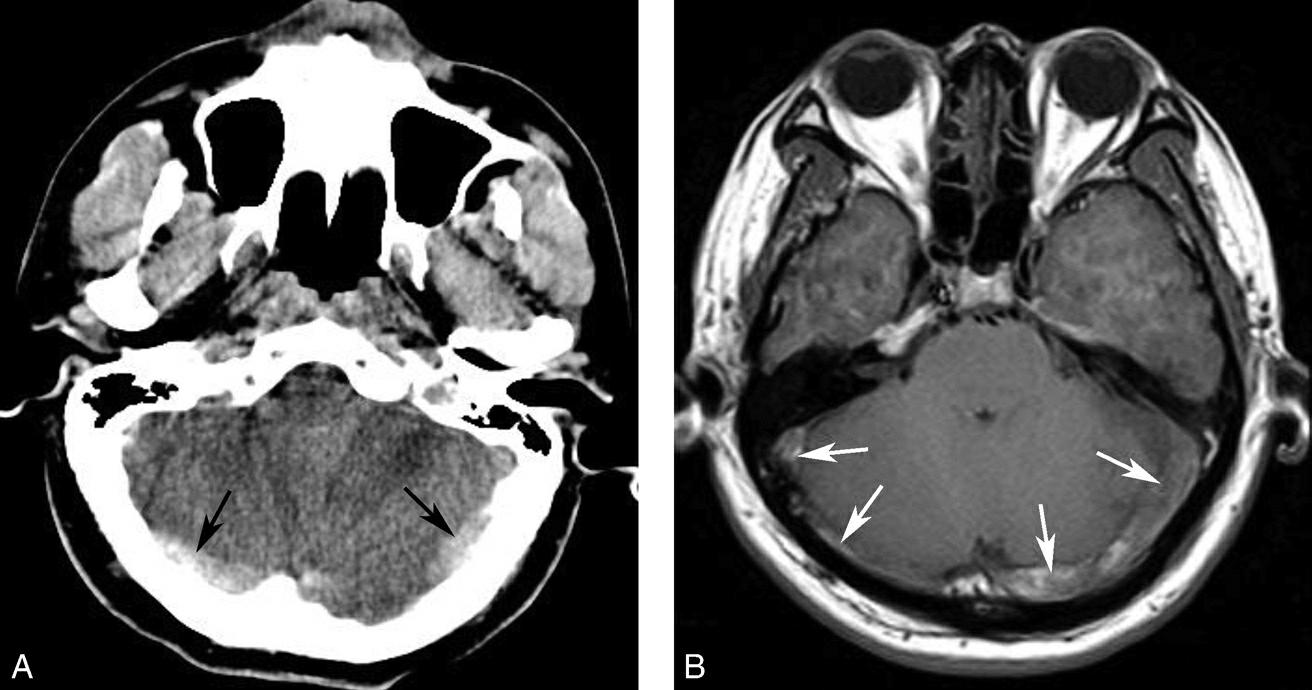

图1-2-14 静脉窦增宽、密度升高(静脉窦血栓)

男,47岁,头痛2周,意识模糊2天,无头颅外伤史。A.CT平扫示双侧横窦增宽、密度增高(黑箭),提示静脉窦血栓;B.MRI T 1 WI提示双侧乙状窦、横窦血栓形成(白箭)